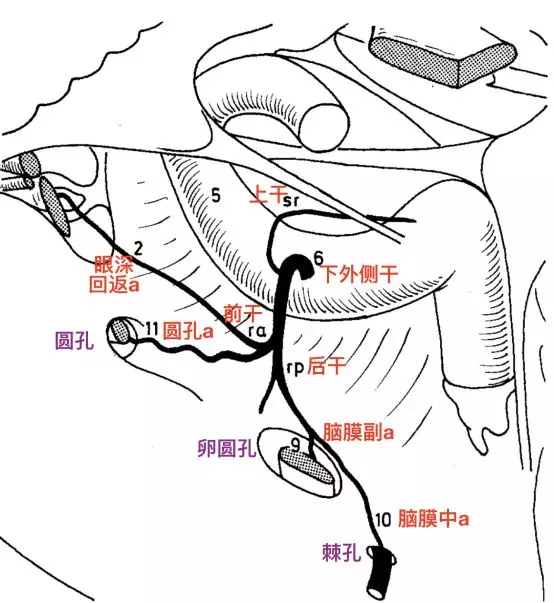

要注意在正常情况下,从颈内动脉海绵窦段发出的下外侧干,可能有分支至圆孔处,与上颌内动脉发出的圆孔动脉有吻合。

海绵窦区发出下外侧干的分支模式图(Lasjaunias 1977)。

在颈内动脉起始段狭窄或者闭塞时,上颌内动脉翼腭段可能通过两个分支,对颈内动脉代偿供血。其一通过翼管动脉,经翼管至破裂孔,与颈内动脉岩段发出的翼管动脉吻合代偿供血。其二就是通过圆孔动脉,经圆孔入颅,在圆孔附近与颈内动脉海绵窦段发出的下外侧干形成代偿供血。

三叉神经分支的动脉血供(Levitt 2011)。V2(星号)由圆孔动脉供血(直箭),V3由脑膜副动脉(空箭)供血。注意圆孔动脉内超选的微导管,以及该动脉特征性迂曲走行。还可见翼管动脉,经翼管走向破裂孔。